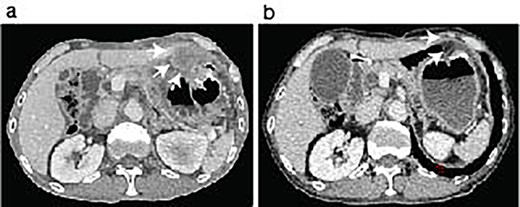

The patient was discharged 3 weeks after the second abdominal surgery. Because the growth of the peritoneal dissemination of the metastatic pleomorphic carcinoma was observed in the follow-up CT scans (Fig. 3a) at 2 months of the second abdominal surgery, the patient underwent immune checkpoint inhibitor (ICI) therapy using pembrolizumab after the final abdominal surgery. The ICI was significantly effective (Fig. 3b), and the patient has remained cancer-free state at 26 months since the first surgery.

ICI therapy after the abdominal surgery. The patient showed peritoneal nodules (arrows) in the first follow-up CT scan after the last abdominal surgery (a). The peritoneal nodules were almost disappeared after 6 months following Pembrolizumab treatment (b, arrows).